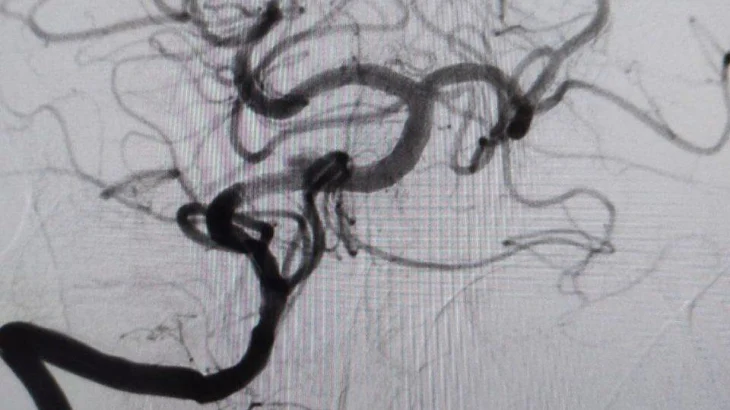

- У пациента был выявлен атеротромбоз - тромбоз на фоне атеросклеротической бляшки - основной артерии, которая обеспечивает кровоснабжение важнейших отделов головного мозга. Это очень тяжелое состояние с крайне высокой летальностью. К счастью, мы успели вовремя, и операция прошла успешно, - рассказала заведующая больницей Элеонора Тулякова.